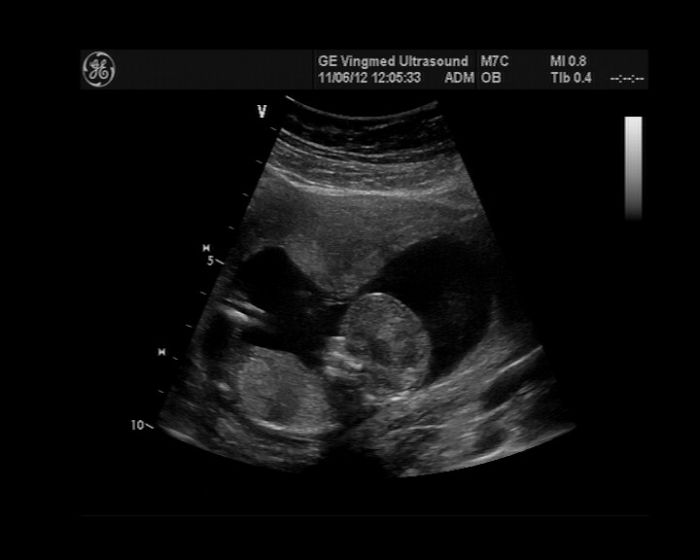

Tak ja take pridam...tady jsme ale jeste malinky...ted uz se na jedno foto nevejdeme